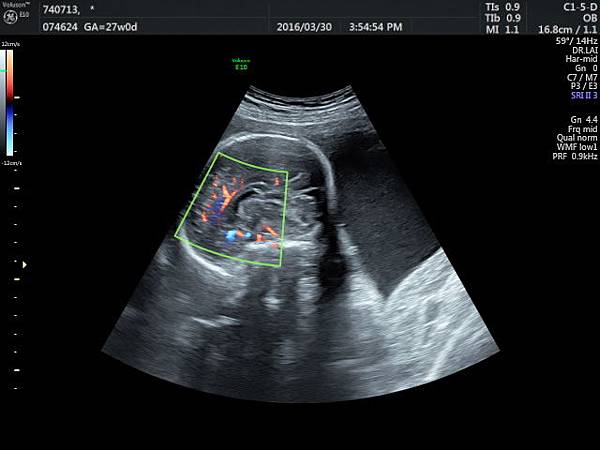

檢查胎兒駢胝體是有技巧的,需要兩個切面:

1. 矢狀切面(sagittal plane):駢胝體呈現類似三明治的中間黑色部分,上面一層薄薄白色的區域是callosum sulcus,打上flow可以看到pericallosum artery在駢胝體上面的周圍,pericallosum artery來源是前腦動脈,參考附圖 6~10,三明治下面白白的部分是和CSP做比較得到的,如果這一層長lipoma(附圖 5),CSP很可能看不到。

2. 冠狀切面(coronal plane):一般只能看到駢胝體genu 的部分,無法很完整的看整個駢胝體。

3. 要看完整的駢胝體,我的經驗是胎頭臉朝上比臉朝下好。(附圖 11~14)